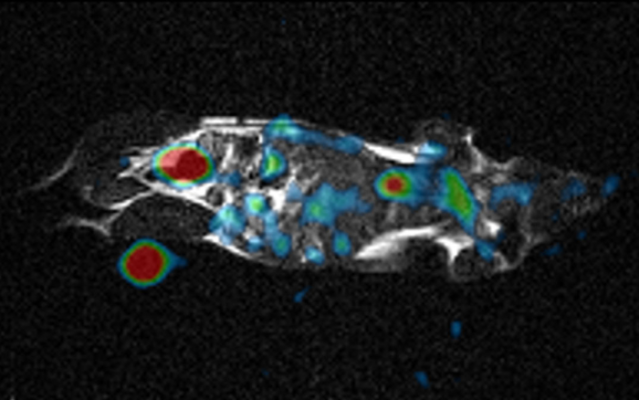

The research team tested the system with a saline “phantom” and an anesthetized mouse. Even though the resulting signal was much lower compared with custom-built 23Na machines, it could be amplified to produce comparable images. “Watching the motion of sodium ions inside the body provides detailed metabolic information not available from conventional MRI images,” Professor Terada says. 23Na imaging has already been shown to be useful for applications involving the kidney, owing to its large sodium concentration, as well as the brain and heart. This approach may substantially reduce health care costs by providing completely new abilities to existing machines without requiring a complete refurbishment.